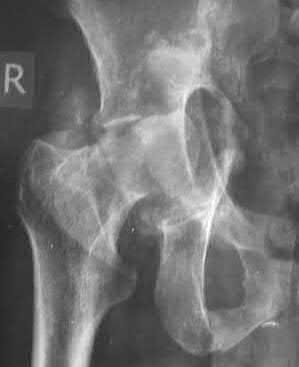

3. # Which of the following is not an appropriate implant for treatment of the fracture seen in Figure A?

5. Sliding hip screw Corrent answer: 5

The image shows a reverse obliquity intertrochanteric hip fracture.

According to the referenced article by Haidukewych et al, unstable peritrochanteric hip fractures have a worse outcome (failed in 9/16 cases) if treated with a sliding hip screw. Two additional factors that were found to have a strong correlation with postoperative failure (nonunion, loss of reduction) were poor reduction and poor implant placement. In this study, fixed angle devices were superior. Intramedullary fixation has the added advantage of a shorter lever arm and less potential for fracture collapse and limb shortening.

The IMN also acts as a medial buttress.

According to Sanders et al, the dynamic condylar screw (DCS) can also be used in subtrochanteric models, but should not be used if extensive comminution is seen, as they reported a high failure rate with DCS in these fractures if highly comminuted. They report a 77% overall union rate with this device.